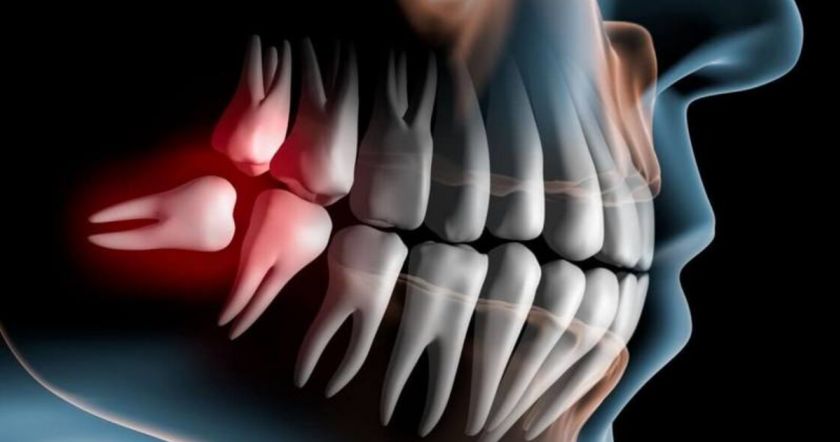

Իմաստության ատամները ռուդիմենտներ են

Մի ժամանակ իմաստության ատաներն օգնում էին մեր նախնիներին շատ կոպիտ սնունդ կտրել, ինչպես նաև ընդեղենը կեղևները կոտրել։ Ժամանակակից մարդիկ դրա կարիքը չունեն, այդ իսկ պատճառով բնակչության 35%-ի մոտ արդեն իսկ չեն աճում իմաստության ատամներ։ Սա կապված է այն հանգամանքի հետ, որ բերանի խոռոչը բավականին փոքր է դրանք տեղավորելու համար։

Երբ որևէ օրգան կամ դրա մաս երկար ժամանակ չի օգտագործվում, այն ռուդիմենտար բնույթ է ձեռք բերում և ի վերջո անհետանում։ Գիտնականները կարծում են, որ ապագայում մարդիկ չեն ունենա իմաստության ատաներ, ապենդիցիտ և ոտնաթաթի ճկույթներ։